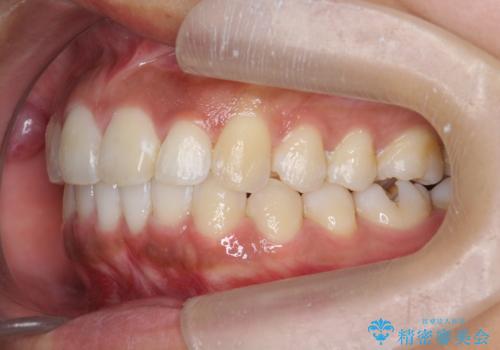

出っ歯感のある前歯を治したい、抜歯をしないマウスピース矯正

- 前歯のガタつき、突出感のある前歯の改善を求めて来院されました。

前歯の角度を改善し審美性を高めるとともに、奥歯のガタつきも並べ直すことで安定した咬合関係の確立を目指します。

歯列の側方拡大をしっかりと行ったことで歯を抜かずに前歯の角度をしっかりと改善することができました。